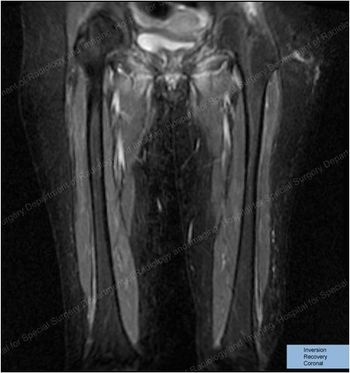

She presented with such severe calf pain she could no longer walk unassisted, with a months-long history of fever of unknown origin. What does the MRI show?